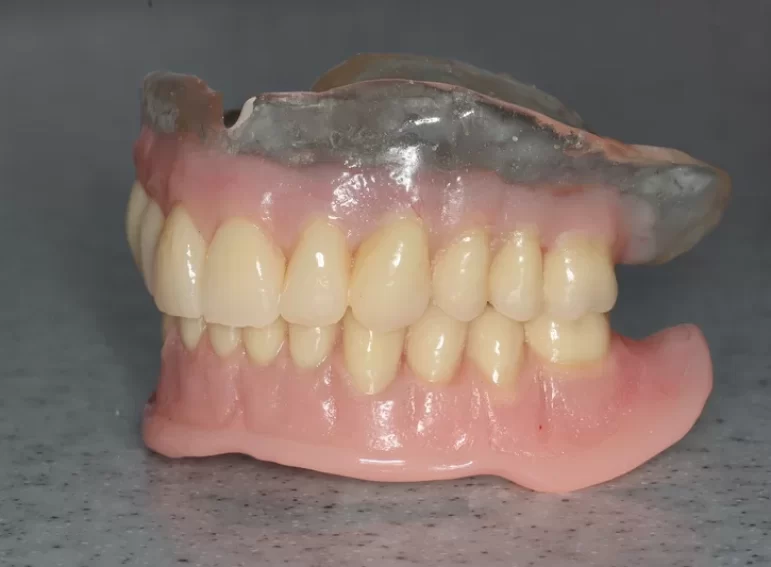

Case 37 – Implants

Upper complete denture and lower implant retained complete denture